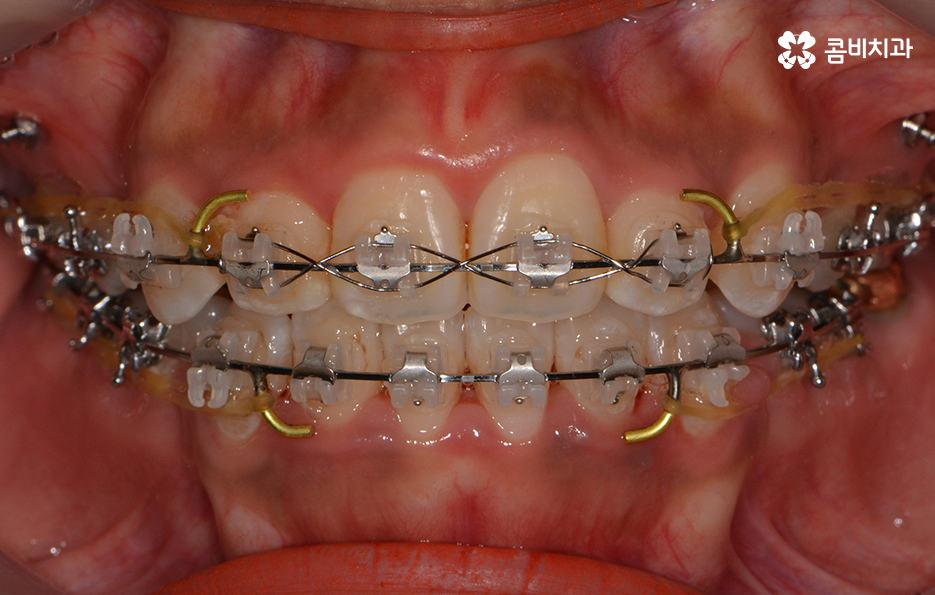

교정이 시작된 후 경과 - 발치를 했던 부위의 치아 사이 빈 공간이 사라짐

전체 교정을 해야 하는 경우에 클리피씨교정을 선택하시는 분들이

많은 이유는 그만큼 타 방법에 비해서 장점이 많기 때문입니다.